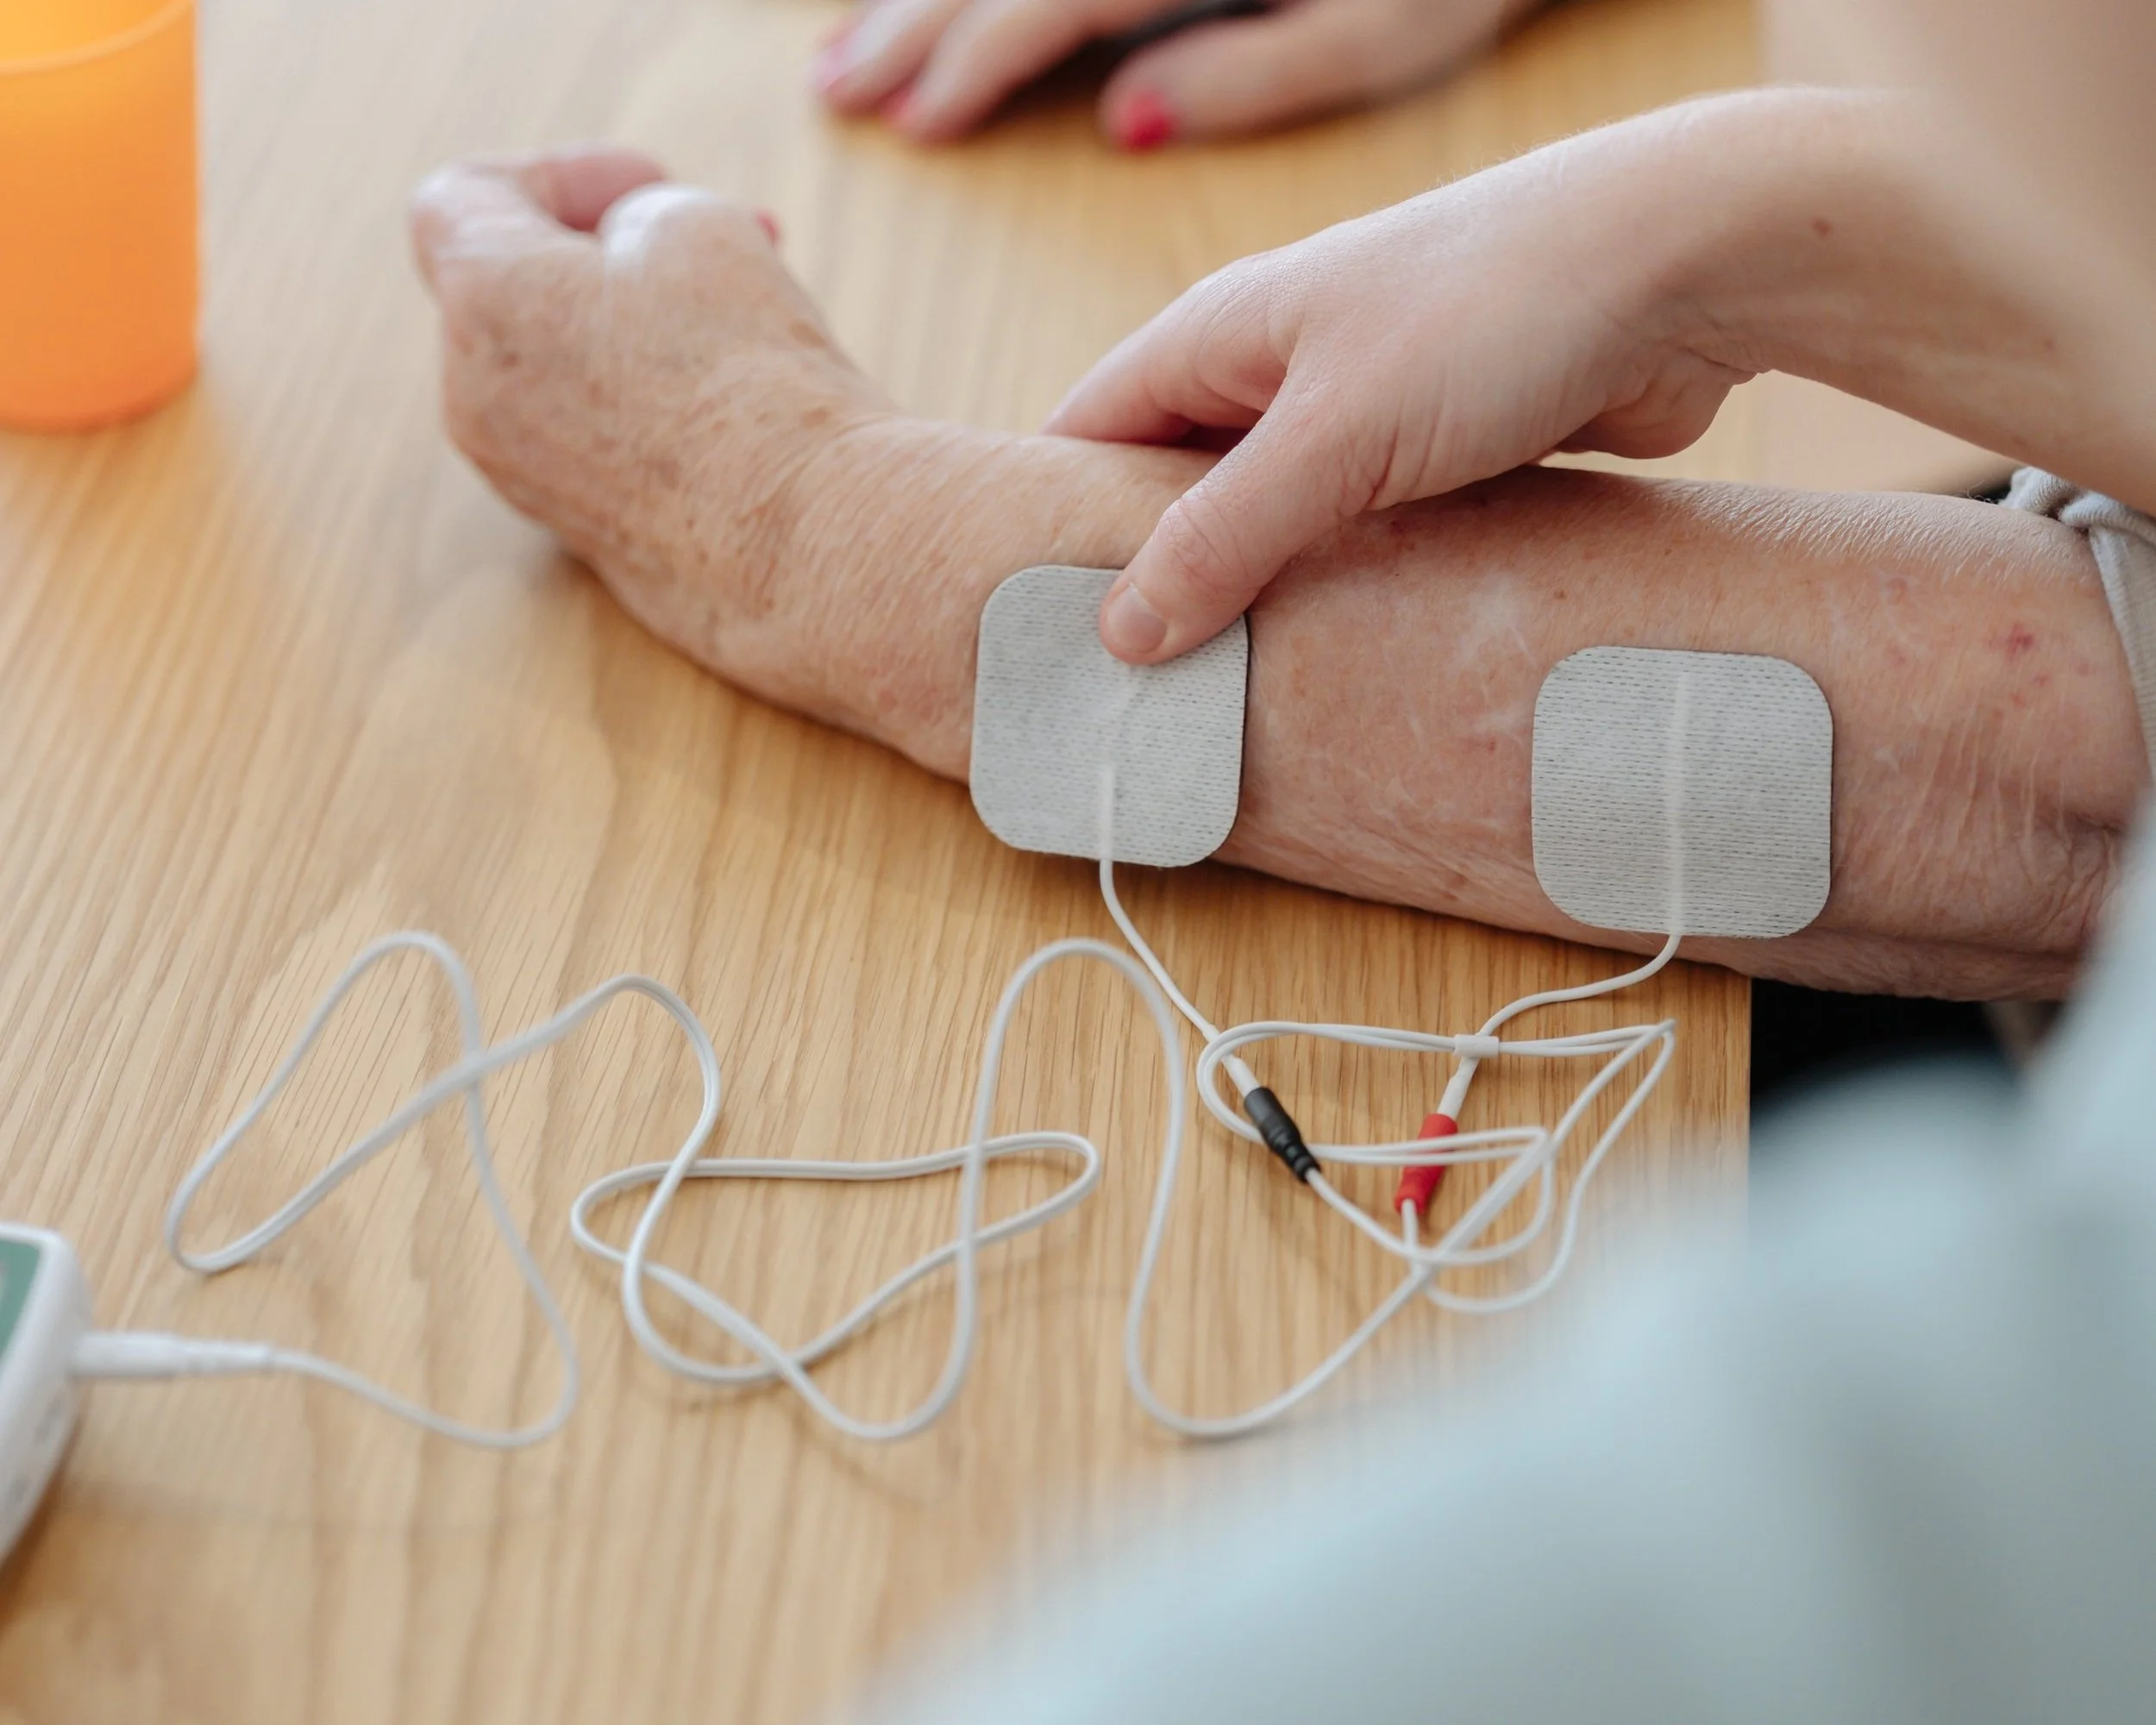

FES uses small electrical pulses to activate weakened muscles, helping to improve movement and function. It’s often used to support walking, hand function, or muscle strengthening.

Shoulder care and device use - electrical stimulation